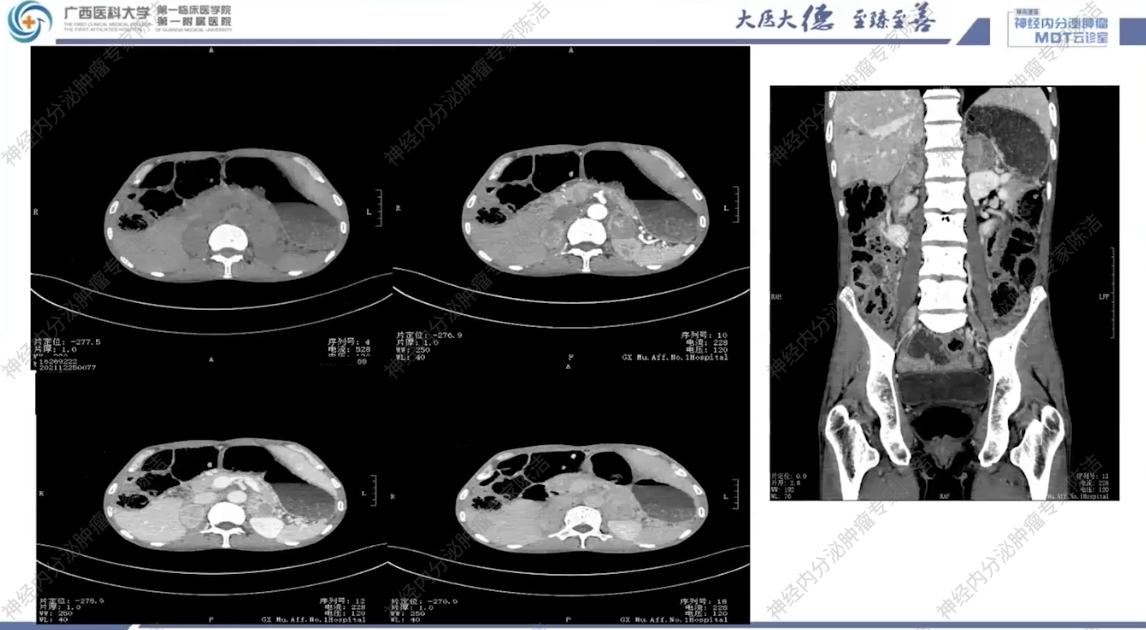

2021年12月13日,当地县人民医院就诊:CT检查提示:1.腹主动脉CTA未见明显异常;2.两侧肾上腺占位,结合临床首先考虑肾上腺髓质来源病变,嗜铬细胞瘤可能性大,未能除外肾上腺转移瘤及肾上腺皮质癌;3.腹膜后小淋巴结,4.十二指肠壁轻度增厚,拟炎症;结肠明显扩张、积气,5.间位结肠。

CT:双侧肾上腺占位伴双肺多发结节,考虑恶性嗜铬细胞瘤伴肺转移可能性大;同时可见双肾囊肿、肠郁张、双肺慢性炎症及肺气肿。

影像诊断科汤伟教授:影像学上,患者双肺多发结节,边界清晰,高度怀疑为转移瘤。腹部CT可见肠管明显扩张积气,呈肠梗阻样改变,符合巨结肠的表现。双侧肾上腺可见富血供的占位,符合嗜铬细胞瘤。垂体MRI平扫虽未做增强,但冠状位可见垂体左侧有低信号微腺瘤的可能,建议行垂体薄层动态增强扫描以明确诊断。